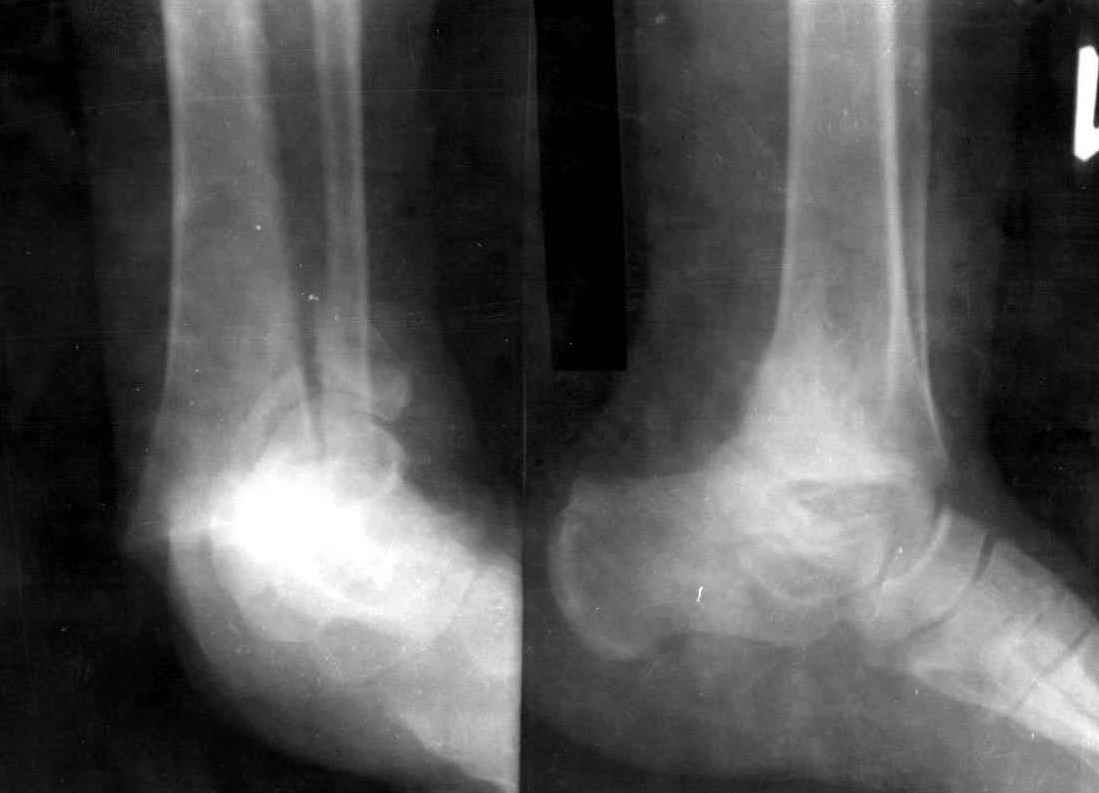

На 4-й неделе убрал спицы, с 7-й недели начал ЛФК, дозированную нагрузку, физиопроцедуры, массаж. Назначил хондропротекторы. Получилось вот что.

Удалены спицы, а гипса не было? 3-х лодыжечный перелом фиксировать 4 недели недостаточно. Что и подтверждается на последнем снимке - есть тенденция к подвывиху кнаружи, кзади... Что будет дальше, когда пациент начнет давать полную нагрузку?

Малоберцовая выглядит коротковатой. Профиль как-то мутный. Вообще, неплохо было бы сделать снимки в сравнении со здоровой.

Получился ожидаемый результат. Недостаточная длительность иммобилизации - подвывих, а жаль, первичная репозиция была замечательная, целесообразность назначения хондропротекторов, физиопроцедур вызывает сомнения.